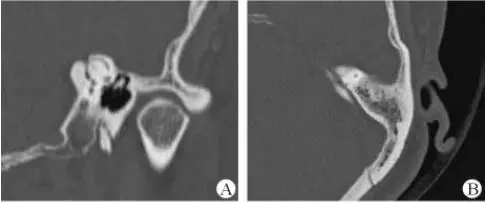

診斷及治療

醫生若懷疑此病將會安排內耳CT掃描。在大多數案例中,一旦此病被耳鼻喉科醫生或其它聽力健康專家確診,則可實行手術治療。外科手術風險包含聽力損失以及神經損傷;重建及復原需內耳的治療以及大腦的重塑。

2、膽脂瘤

另一個不常見的疾病叫膽脂瘤,發病率為1/10000,這個“腫瘤”在內耳中逐漸生長。盡管不是惡性的,但也能導致永久性的聽力損失以及其它嚴重的疾病,比如腦膜炎。癥狀是有臭味的耵聹以及聽力損失。

先天性膽脂瘤,長在鼓膜后并在出生時已存在。醫學專家認為這種情況是由皮膚細胞在錯誤的地方生長造成。獲得性膽脂瘤,常發生于成人,這些人患有慢性或反復性耳部感染。

幸運地是,醫生在耳部檢查的時候能看到珍珠白樣的聚集物。大部分的膽脂瘤能通過外科手術移除。若不處理,膽脂瘤將長大并漫延侵潤,造成內耳結構的永久性破壞導致眩暈以及平衡問題或面部神經以及肌肉的破壞,造成麻痹。

膽脂瘤一旦被感染,毒性將被拓展至其它部位,將會造成非常罕見的腦膜炎和腦膿腫。